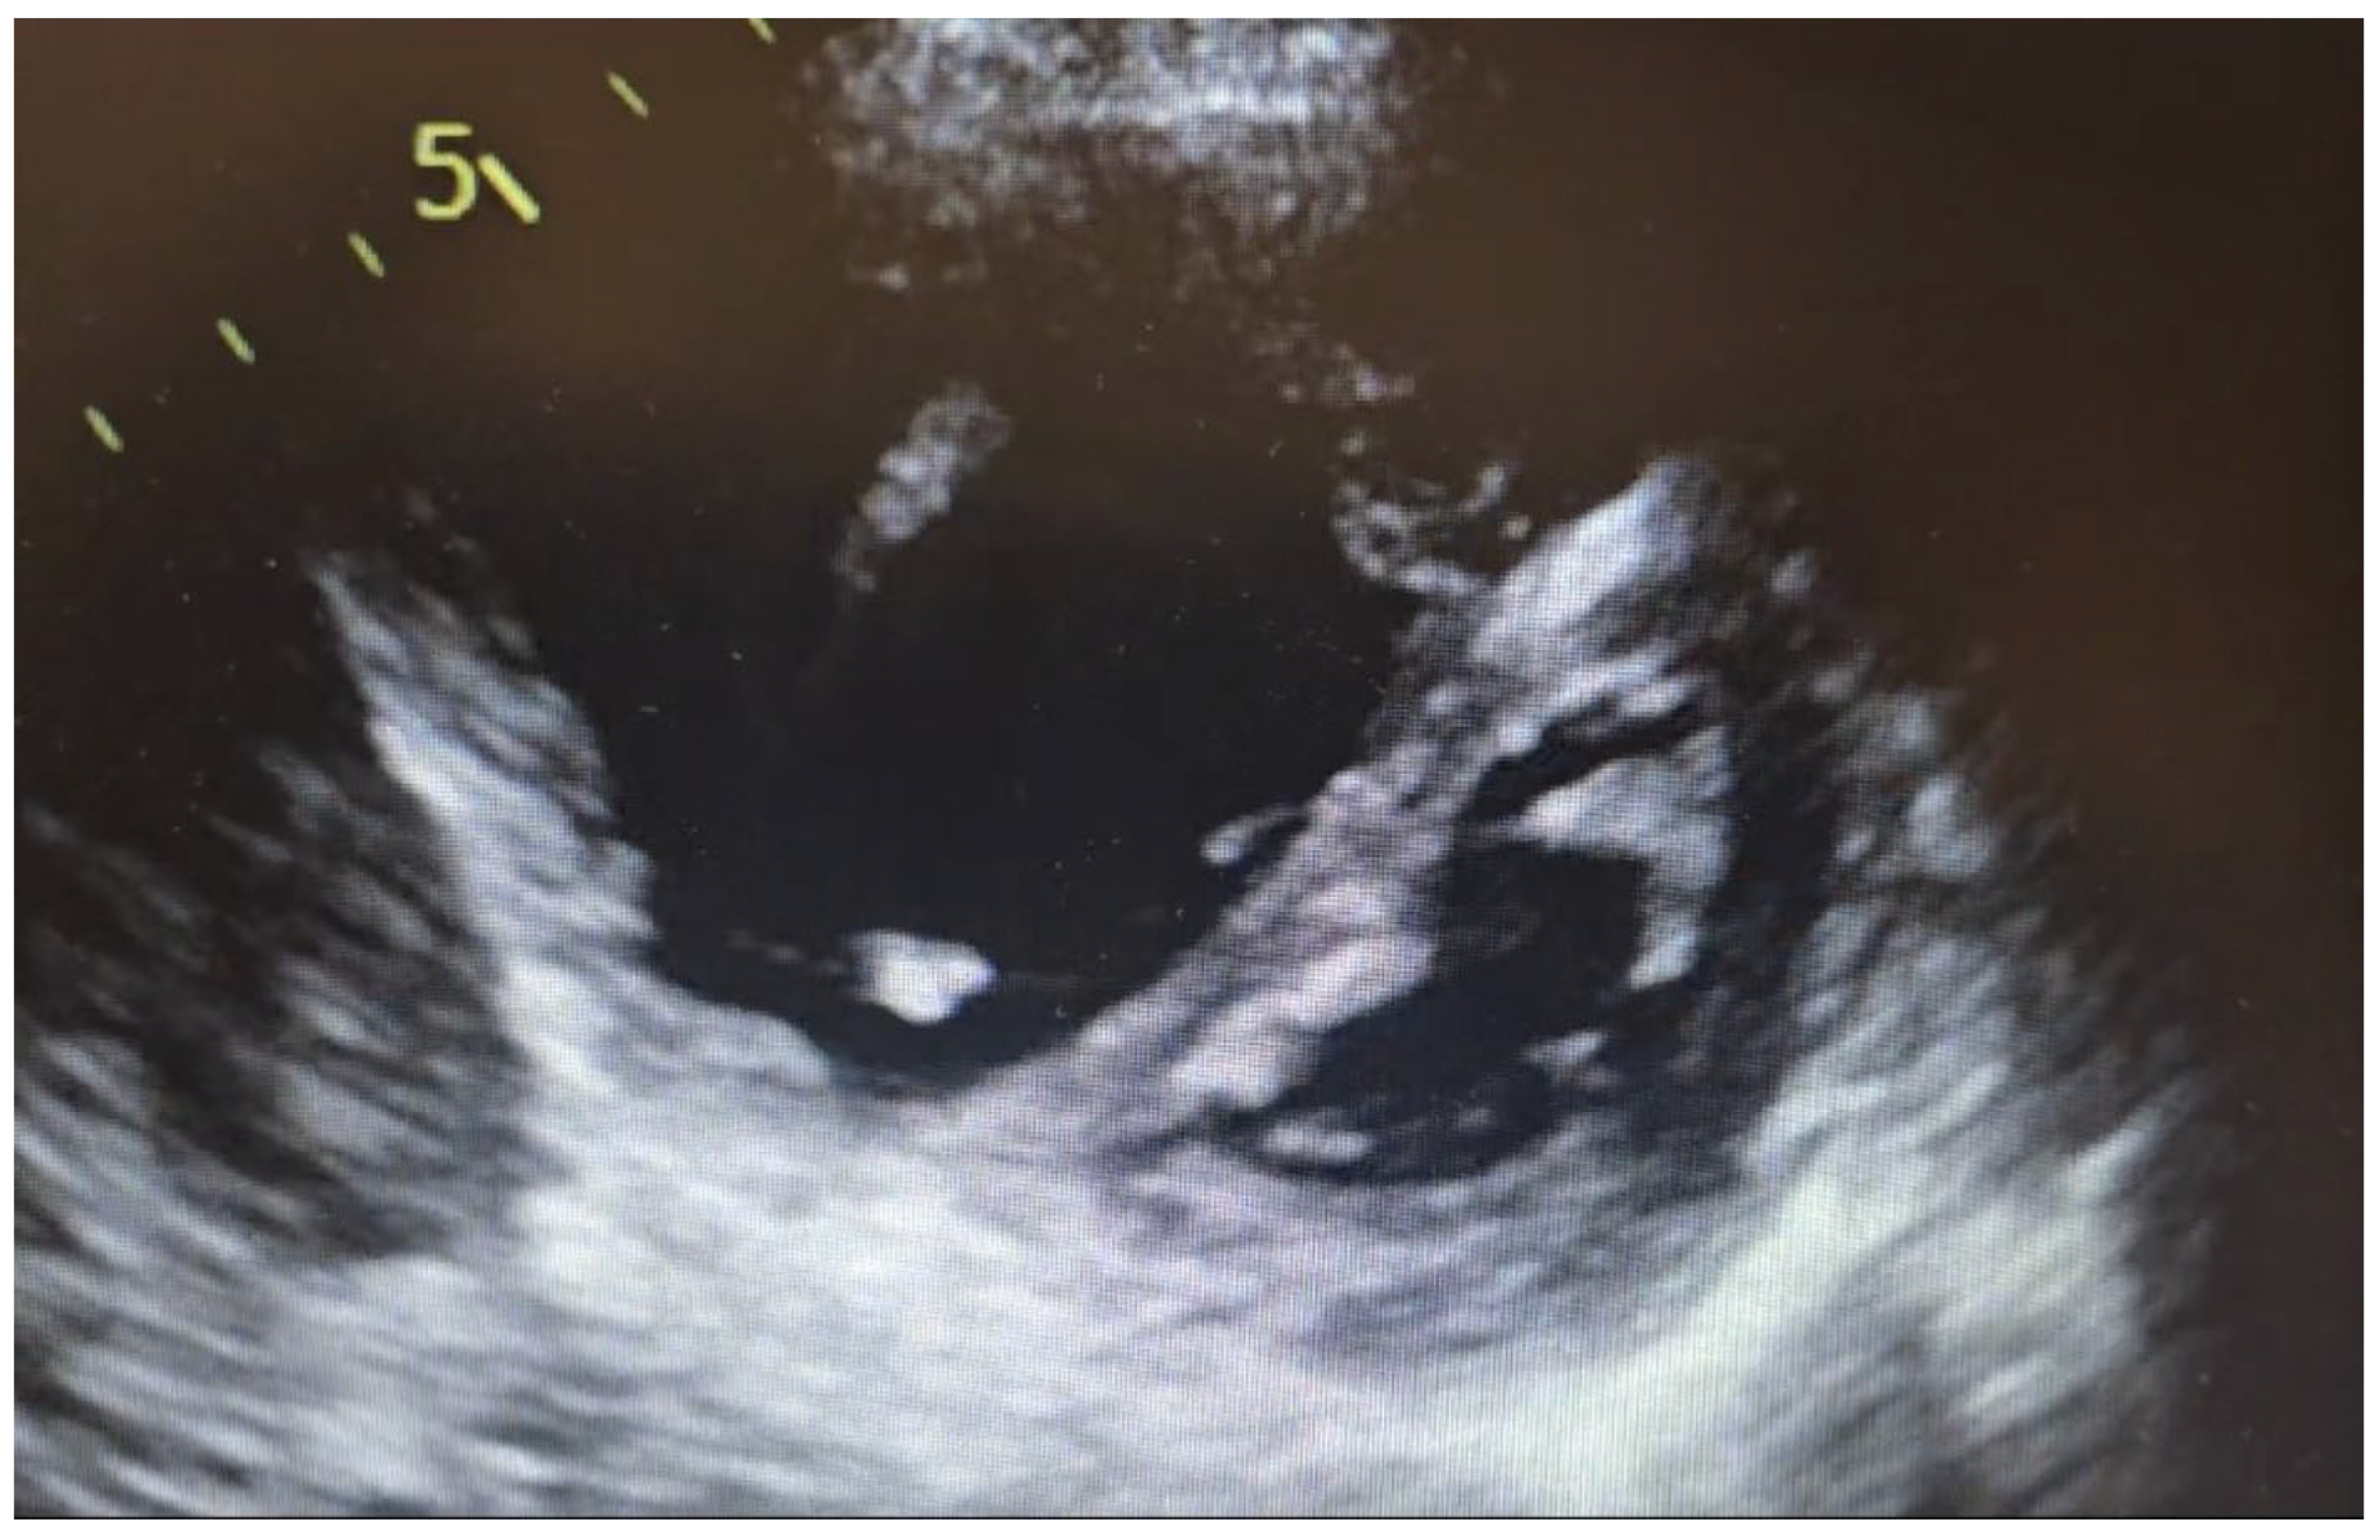

4. Imaging Characteristics on MRI